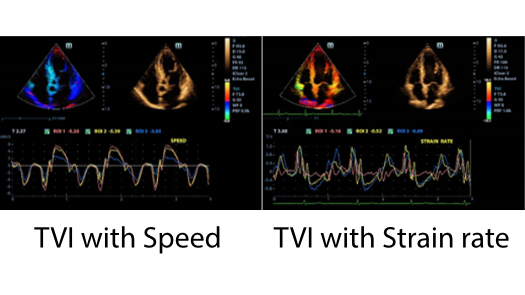

Tissue Doppler Imaging(TDI)

- Несколько режимов тканевого доплера TDI: TVI, TEI, TVD и TVM

- Поддержка сравнительного анализа в реальном времени и в автономном режиме